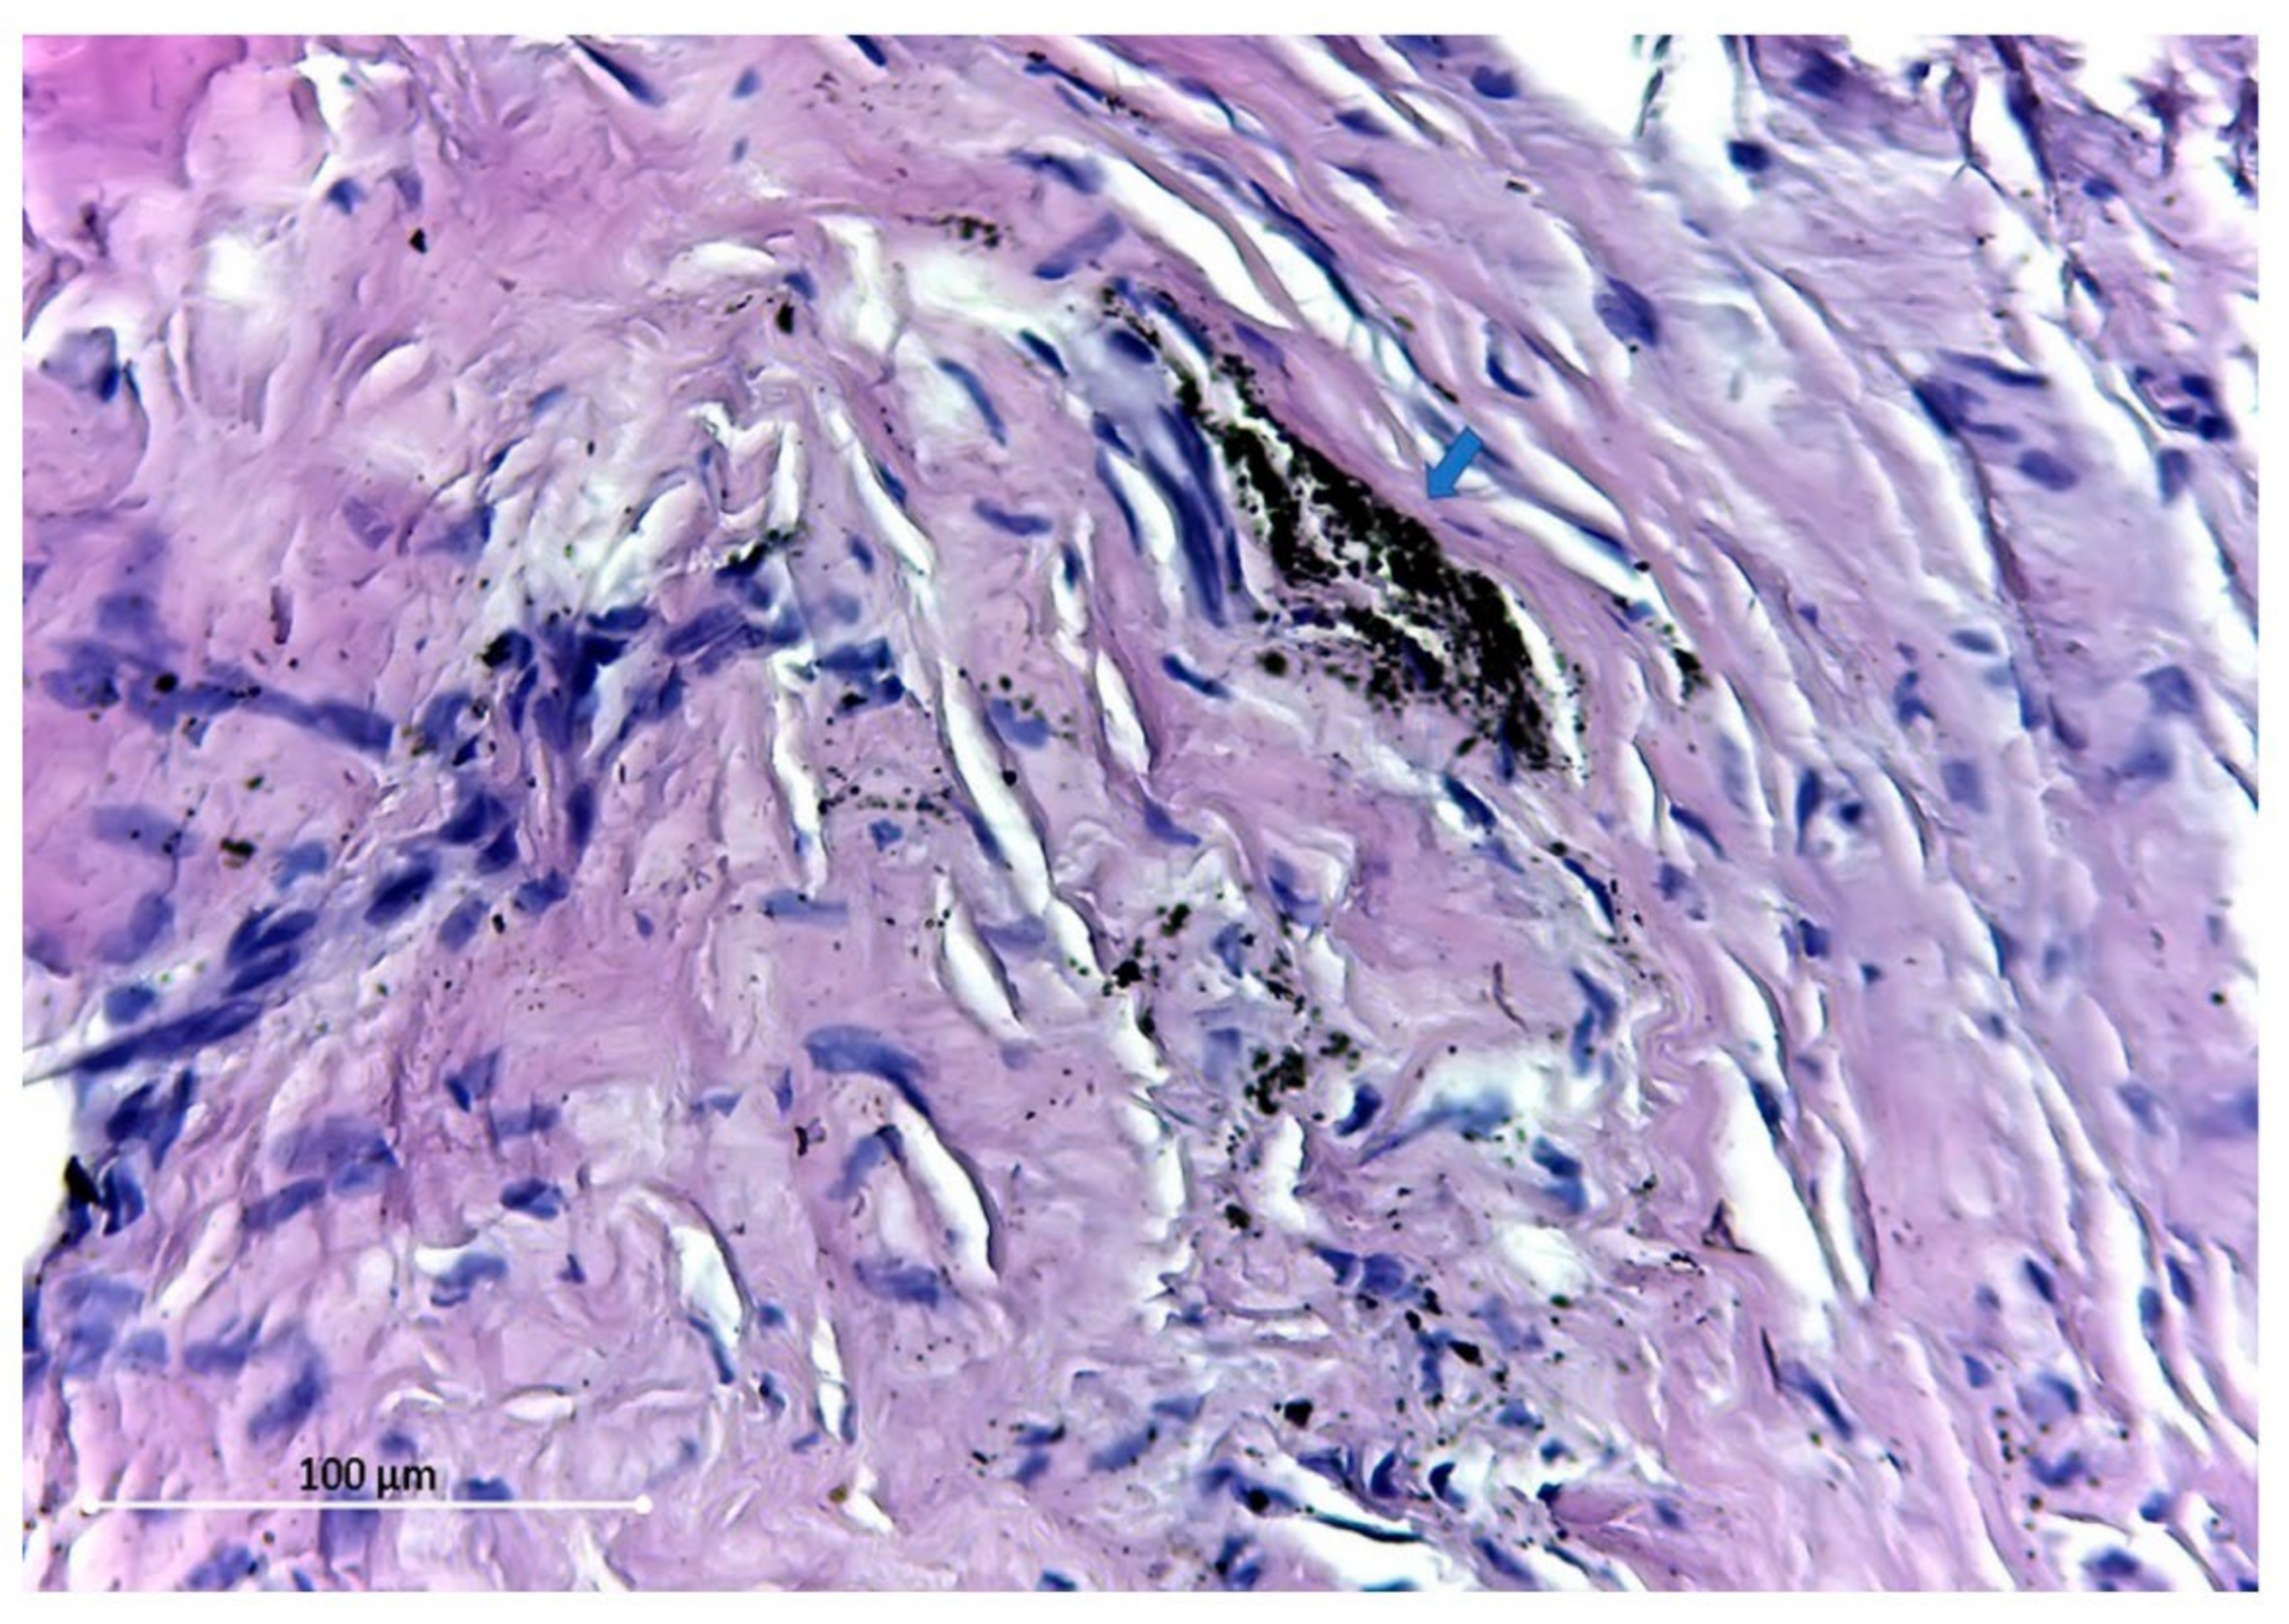

- Armencea, G.; Gheban, D.; Onisor, F.; Mitre, I.; Manea, A.; Trombitas, V.; Lazar, M.; Baciut, G.; Baciut, M.; Bran, S. Histological Change in Soft Tissue Surrounding Titanium Plates after Jaw Surgery. Materials 2019, 12, 3205. [Google Scholar] [CrossRef]